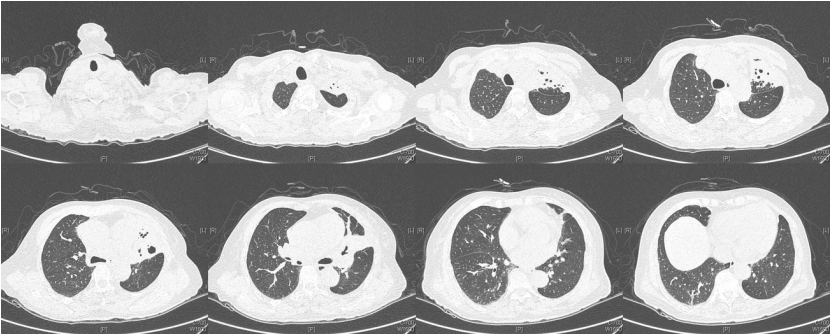

由于厌氧菌培养非常困难,既往我们对厌氧菌的认知仅限于在消化道定植,对其致病机制以及何种情况下致病并不非常清楚。厌氧菌定植于皮肤黏膜,是一种内源性微生物,感染发生率高,可导致严重、致死性感染。由于标本采集和转运的特殊性,使厌氧菌难以分离;加之其培养困难,体外生长慢,所以既往很难识别。厌氧菌在治疗方面存在一定挑战,如往往混合多重感染,且易产生耐药,也会因治疗延迟导致治疗失败。随着近10年来NGS技术的应用和普及,我们对厌氧菌的认识得以提升。常见的致病厌氧菌分为革兰阳性球菌、革兰阴性球菌、革兰阳性非芽孢杆菌、革兰阳性芽孢杆菌以及革兰阴性杆菌(表1)。革兰阳性非芽孢杆菌中可能致病的是放线菌,例如龋齿放线菌参与龋齿的发病过程。革兰阳性芽孢杆菌往往具有致病性,其中产气荚膜杆菌、艰难梭菌/难辨梭状芽孢杆菌、肉毒杆菌/肉毒梭菌、破伤风梭菌/杆菌具有强致病性。革兰阴性杆菌中的拟杆菌属对青霉素类药物具有很强的耐药性,易致青霉素治疗失败。临床中我们与厌氧菌的接触逐渐增多,对其特点也会愈发熟悉,对于临床诊断和治疗也会有所帮助。在NGS报告中通常会将检出的厌氧菌列为“C类”,定义为致病性C类—呼吸道正常微生态菌群,一般不导致感染。但当患者存在误吸风险时,需关注厌氧菌引起肺脓肿的可能。此时就需要针对患者的危险因素、临床表现、影像学、病原学以及气管镜下特点等进行综合分析。微小单胞菌最早是通过培养进行鉴定。瑞士2015—2022年132例病例报告的培养鉴定结果显示,血液中检出微小单胞菌37例(28%),肺内(肺脓肿、脓胸)检出29例(22%),总体病死率较低(5.3%)。国内周华教授团队开展的一项回顾性研究分析了2019年1月至2020年7月经病理活检和mNGS诊断的5例与微小单胞菌相关的慢性肺脓肿患者。患者的平均病程为6.5个月,共同特征是口腔卫生差,有酗酒史,且CT表现为边界不规则的高密度团块状实变影,并且在病灶中间可见液化性坏死,但没有发现气液平面或空腔,所以前期易被误诊为肺癌。下图1是该研究报告中病例3的肺部CT表现。时间点1:首次就诊时,左下叶可见团块状肺不张,伴周围磨玻璃样渗出病变,中心坏死不明显,可见细小空气囊泡影。时间点2:发病8个月时,可见大面积肺实变,增强CT示病灶内有液化坏死和小空洞。时间点3:经过3个月的有效抗厌氧菌治疗,病灶明显缩小,遗留空洞和纤维增殖病灶。图2是病例4的肺部CT表现。时间点1:患者首次就诊时,右上叶可见肿块样肺部实变影。时间点2:发病8个月时增强CT,可见实变明显增大,病灶内出现液化坏死。时间点3:经过3个月的有效治疗,病灶明显缩小,有残留空洞和纤维瘢痕样病变。由于通过影像学鉴别该病与肺癌具有挑战性,所以5例患者都接受了支气管镜检查和CT引导下经皮肺活检。5例患者经组织活检或支气管肺泡灌洗液(BALF)标本mNGS检测到微小单胞菌。病例: 女性, 67岁, 主诉"咳嗽咳痰2个月"。现病史:2个月前,患者家属感染新冠病毒(家属新冠抗原阳性)之后,患者出现咳嗽咳黄脓痰,无痰中带血及痰液拉丝,痰无臭味,无胸闷气短及胸痛,无咽痛咽痒,无鼻塞流涕。6月9日于当地市医院住院,住院期间出现发热,体温最高38.6℃,无寒战,查新冠病毒核酸阳性,予先诺特韦/利托那韦片口服治疗。查胸部CT见左肺上叶软组织影,左肺上叶炎症。诊断肺脓肿,予头孢唑肟联合莫西沙星,治疗后复查胸部CT(6月26日)病灶较6月9日明显吸收好转。6月14日气管镜检査见左肺上叶支气管开口狭窄,见大量脓性痰液堵塞支气管开口(病原学结果家属无法提供)。6月30日办理出院后仍有咳黄脓痰,无发热畏寒,口服止咳化痰药物,未使用抗生素。7月30日复诊胸部CT见左肺上叶异常密度较前增大。8月2日再次于当地市人民医院住院。8月4日气管镜检查: 左肺上叶黏膜肿胀肥厚, 管腔狭窄, 见大量白色干酪样分泌物涌出, 支气管镜不能进入。内科予莫西沙星静滴治疗10天, 外科予莫西沙星联合哌拉西林他唑巴坦静滴9天。复查胸部CT见病灶较前进展, 且右肺出现新发感染病灶。病程中患者饮食可, 睡眠差, 二便正常, 体重减轻5 kg。既往对阿莫西林过敏, 表现为口服阿莫西林后全身皮疹。否认嗜酒史及吸烟史。入院后胸部增强CT可见病灶内液化坏死,同时伴有小的空气囊泡影(图3)。患者有胸痛症状。气管镜检查发现气道内有痰栓或黏液栓阻塞征象(图4)。灌洗液tNGS结果回示:微小单胞菌(序列数2762),巨细胞病毒(序列数171),副流感病毒(序列数79),EB病毒(序列数61)。考虑病毒不会导致气道内如此改变,但由于微小单胞菌属于常见口腔定植菌,此时也不能完全确定微小单胞菌是否为引起感染的主要责任病原体。8月24日起予莫西沙星0.4 g qd ivgtt+哌拉西林他唑巴坦4.5 g q8h ivgtt。经过上述治疗,患者局部病灶有所吸收,但整个肺叶并无明显改善(图5)。气管镜检查仍然发现气道内有较黏稠的黏液栓阻塞气道开口(图6)。治疗经过:气管镜下予以局部冲洗,再次送检tNGS。9月7日结果回示:微小单胞菌(序列数6464),较前明显增多;副流感病毒(序列数998),EB病毒(序列数331)。9月9日起调整治疗方案为美罗培南1 g q8h。9月12日复查患者胸部CT,可见肺通气部分改善,肺组织内实变较前吸收(图7)。第三次气管镜检查仍可见少量痰栓嵌塞在远端支气管开口(图8)。患者此后转入医联体医院继续抗感染治疗。病例2:女性,54岁。主诉:咳嗽咳痰2个月,发热1周。现病史:入院2个月前,患者在西南地区旅游时感冒,出现咳嗽咳痰,白痰为主,量多,无胸痛,无发热,无痰中带血,咳时气短。于河北某诊所间断输液治疗14天(具体不详),期间口服中药治疗,症状未缓解。入院3周前(2023-09-07)就诊于当地县医院,查胸部CT提示右肺炎症,静脉滴注氨曲南、左氧氟沙星、氨溴索治疗1周,症状未缓解。2023年9月14日复查胸部CT显示右肺炎症较前加重,于当地中心医院住院。动脉血气分析:pH 7.43,PaCO2 38.4 mmHg,PaO2 67 mmHg,SaO2 94.2%;血沉90 mm/h;生化:白蛋白35.3 g/L;CRP 82.7 mg/L;血常规:WBC 9.75×109/L,NEU 6.83×109/L,HGB 104 g/L。静脉滴注莫西沙星。入院10天前,行肺穿刺活检,病理回报为少量肺组织及纤维结缔组织,炭末沉积,较多中性白粒细胞、淋巴细胞及浆细胞浸润,伴脓肿形成;肺穿刺mNGS结果回报:微小单孢菌(序列数2650),鲍曼不动杆菌(序列数17),人类疱疹病毒4型(序列数60),人类疱疹病毒7型(序列数5),文氏密螺旋体(序列数4337),解卵磷脂密螺旋体(序列数1121),齿垢密螺旋体(序列数698)。调整抗生素为头孢哌酮舒巴坦2 g q12h。入院1周前,出现发热,体温最高38.5℃,不伴寒战,咳嗽咳痰无加重,无咯血;复查血常规、PCT、CRP均明显增高(未见报告单);复查胸部X线提示右肺炎症范围增大,右侧胸腔积液。更换抗生素为哌拉西林他唑巴坦4.5 g q8h。4天前,支气管镜下见右肺下叶背段支气管略狭窄,黏膜水肿,可见脓性分泌物溢出。BALF革兰染色查见革兰阴性杆菌,抗酸染色、霉菌未见异常,培养未回报。患者体温逐渐降至正常,咳嗽咳痰有所减轻,复查胸部CT提示右肺高密度影,右侧胸腔积液较前增多。为求进一步诊治来我院就诊被收入院。既往甲状腺功能减退病史5年,目前口服优甲乐治疗,监测甲状腺功能指标在正常范围。20年前因宫外孕行手术治疗。2023年10月8日胸部CT示胸膜下斑片状坏死,纵隔窗可见微小空气囊泡影及密度不均匀液化坏死(图9)。治疗:9月28日至10月13日莫西沙星0.4 g qd ivgtt+哌拉西林他唑巴坦钠4.5 g q8h ivgtt。最终患者病灶吸收好转并顺利出院。患者男性,42岁。主因间断咳嗽、咳痰1月余,左侧胸痛、气短2天入院。现病史:入院前1月余(2022-07-19),患者无明显诱因出现咳嗽,咳白痰,痰中有少量鲜红色血丝,左侧胸痛(为钝痛),深吸气后加重,就诊于当地医院。完善肺动脉CTPA:示左上肺动脉舌段分支局部管腔可见线条样低密度充盈缺损,考虑肺栓塞;左肺上叶实性病变伴不均匀强化,性质待定,部分为肺梗死改变可能,纵隔多发稍大淋巴结,性质待定;右肺下叶后基底段可见一不规则实性结节,边缘可见多发毛刺,直径约0.7 cm。当地医院考虑肺栓塞不除外,肺部感染?右肺下叶结节,予莫西沙星抗感染,低分子肝素抗凝,乙酰半胱氨酸化痰。完善CT引导下肺穿刺活检,病理示:肺泡腔扩张伴上皮轻度增生,肺泡间隔纤维组织增生伴散在炎细胞浸润,未见恶性病变。院外规律应用甲磺酸艾多沙班60 mg bid抗凝,先后间断应用左氧氟沙星0.5 g qd、头孢类抗生素(具体药物、剂量不详)抗感染。患者仍有间渐咳黄白痰,量不多,痰中有少量鲜红色血丝;无畏寒、发热、胸痛、夜间阵发性呼吸困难症状,无尿少、双下肢水肿,无口干、咽干,无牙齿成片脱落,无晨僵、关节肿痛,周身无皮疹,无盗汗乏力。2天前(2022-09-16)患者无明显诱因再次出现左侧胸痛,疼痛剧烈,深吸气、咳嗽及改变体位时加重,伴气短,就诊于我院急诊。完善肺动脉CTPA:肺动脉主干及其各叶段分支未见明显充盈缺损,左肺上叶舌段团块影,最大截面约7.6 cm×5.3 cm,边界不清,周围可见晕征;增强扫描不均匀强化,邻近胸膜增厚,性质待定,建议穿刺活检;纵隔及左肺门多发淋巴结显影。血细胞分析:WBC 11.09×109/L,NEU% 80.8%,NEU 8.95×109/L;CRP 54 mg/L,PCT 0.07 ng/ml。患者自发病以来,精神状、食欲及睡眠均一般,大小便正常,体重下降5 kg。2022年9月14日外院胸部增强CT:胸膜下楔形的影像学表现可见少量小气泡囊以及液化坏死病灶(图10)。初始考虑肺部肿瘤及肺栓塞。经过初步抗感染及抗凝治疗,患者病情无缓解,2022年9月27日患者突发胸痛,下肺影像加重并且出现脓胸(图11)。行胸腔穿刺并将脓液送检mNGS,结果回报:牙龈卟啉单胞菌(序列数3)。尽管序列数很低,但考虑是脓肿穿刺结果,因此考虑该菌致病可能。抗厌氧菌治疗:9月16-28日莫西沙星0.4 g qd ivgtt,9月23日-10月12日美罗培南1 g q12h ivgtt,9月28日-10月8日万古霉素1 g q12h ivgtt,10月13-18日莫西沙星0.4 g qd ivgtt+甲硝唑0.5 g tid ivgtt。患者肺脓肿的整体治疗时间约为3个月,病灶逐渐吸收,最终形成一些纤维索条影(图12,图13)。1年后复查病灶基本吸收(图14)。图14 1年后复查胸部CT(2023-08-08)微小单胞菌和卟啉单胞菌这两种厌氧菌在临床中需要引起重视,它们容易引起肺脓肿/脓胸。2024年国内学者Li Yao等在Diagn Microbiol Infect Dis 杂志发表了一篇牙髓卟啉单胞菌感染所致肺脓肿的病例报告,文章也提到在胸水或肺组织活检中,通过mNGS同时检出了微小单胞菌和卟啉单胞菌感染引起的肺脓肿。文章还回顾总结了既往发表的厌氧菌感染引起肺脓肿的病例,2010年报道的是1例脑脓肿患者,2019年报道1例脑炎患者,2022年报道1例脓胸伴呼吸衰竭患者。3例患者预后都比较好,可见厌氧菌亦可导致肺外多部位感染。对于厌氧菌所致肺脓肿的诊断及其引起的脓胸,目前的文献报道仍然较少,我们对它们的认知也有限,因此也提醒大家关注相关疾病的诊断和治疗。我们也已将本研究小组8例微小单胞菌所致肺脓肿的系列病例的研究结果发表(Front Cell Infect Microbiol, 2024, 14: 1416884),可供需要的同行参考。对于厌氧菌感染,我们需要提高警惕。厌氧菌往往在口咽部定植,其引起的脓肿/感染往往多为亚急性或慢性起病。患者通常有发热、胸痛症状,脓肿会逐渐进展。由于厌氧菌与人体本身是一种长期共生的关系,人体对厌氧菌的免疫识别可能处于较低的防御反应状态,所以会形成一个亚急性或慢性的发病过程。通常情况下,因厌氧菌的菌群发生了移位,从卫生条件不好的口腔扩展到相对无菌的肺内,同时开始增殖,由此可能导致感染。因此,对于酗酒以及口腔卫生非常差的人群,我们要重视对其风险因素和病史的排查。患者就诊时可能病情并不重,有胸痛或咯血,很容易误诊为肺部肿瘤,往往在这种情况下进行肺穿刺或气管镜检查,mNGS可以发现较大序列数的厌氧菌。但在mNGS检出厌氧菌后的诊断过程中又容易形成误判——究竟是致病菌,还是定植菌?此时结合患者其他病史和影像学特点(有脓肿/痰栓形成,微小空气气囊泡影),可能提示厌氧菌感染。然而,厌氧菌感染在病原学和影像学诊断方面仍然存在诸多困难,极易漏诊和误诊。微小单胞菌感染患者在气管镜下可以看到典型的脓性分泌物嵌塞气道,导致气道阻塞,也会造成远端气道和肺泡引流障碍。所以,及时处理气道内痰栓,改善引流,可能是使患者获得良好预后的关键。厌氧菌肺脓肿的吸收比较缓慢,抗感染的疗程也比较长,需要在后期诊疗过程中密切随访和观察患者对治疗的反应以及耐药等问题,及时调整治疗方案,适当延长疗程。